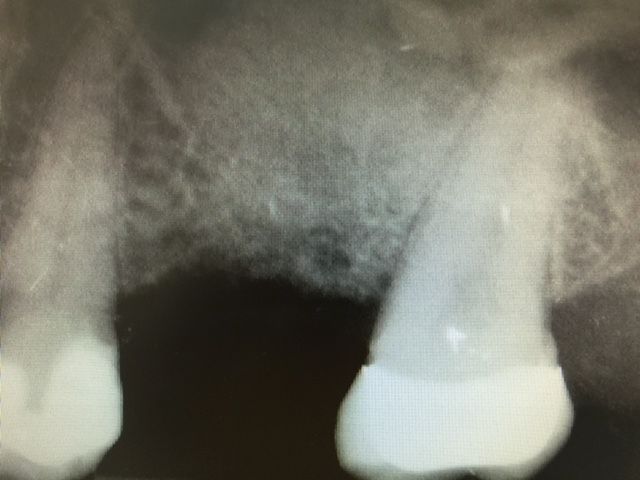

CAS N°2